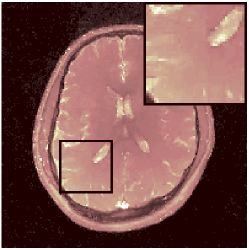

Two sets of experiments were conducted here: first, we used the 2D and 3D acquisition sequences for scanning a healthy volunteer’s brain (real-world acquisitions). Figures 6 and 7 display the parametric maps reconstructed from 2D spiral and radial readouts. We computed the T1, T2 and proton density (PD) maps using baseline reconstruction algorithms ZF, VS, LR, FLOR, AIR-MRF and our proposed LRTV. While baselines use DM either for quantitative inference or also during reconstruction (i.e. AIR-MRF), we further compare the DM-free LRTV’s performance when cascaded to DM, KM and MRFResnet for quantitative inference. For the 3D spiral acquisitions we compared LRTV and its closest competitor VS in Figure 8. Outcomes from other tested algorithm are displayed in the supplementary materials (Figure S5). Since FLOR does not use dimensionality-reduction, our system ran out of memory during 3D reconstruction; hence results are not reported in this case.

VI-E1 Discussion

The LRTV-DM and LRTV-MRFResnet perform on par, and both outperform all tested baselines for reconstructing T1, T2 and PD maps in all acquisition schemes. This can be observed both visually in Figures 6, 7, 8, S2 and S3, and quantitatively in Table IV across all tested metrics. Other baselines were unable to successfully remove the under-sampling artefacts in TSMIs, and these errors propagated to the parameter inference phase and resulted in inaccurate maps. Temporal-only priors incorporated within LR are shown insufficient to regularise the inverse problem and LR sometimes (e.g. 2D spiral acquisitions) can admit solutions with even stronger artefacts than the model-free ZF baseline. This issue was previously studied for other non-Cartesian MRF readouts that similar to our spiral/radial trajectories, miss to sample the corners of the k-space in all timeframes (see section 2.2.2 and figure 2 in [19]). In the absence of reference for the k-space corners information, the LR iterations despite minimising the objective can converge to solutions with high-frequency artefacts, as visible in the computed maps. This highlights the need for adding an appropriate spatial-domain regularisation. FLOR reduces the LR’s artefacts but this improvement is limited because the suggested nuclear norm penalty does not incorporate an explicit spatial regularisation. Further for reducing artefacts, FLOR can introduce an undesirable bias in the computed T1/T2 maps e.g. see error maps in Figures S2 and S3. The non model-based VS baseline incorporates spatial regularisation and results in spatially smoother maps than ZF and LR, but it is unable to output artefact-free images. Further and consistent with our in-vitro experiment, we observe that VS overestimates the T2 values (e.g. in White and Grey matter regions) in tested 2D acquisitions i.e. the spatial regularisation trades off agains the quantification accuracy. The model-based AIR-MRF adds spatial regularisation through 2D/3D low-pass Gaussian filters however this trades off the sharpness of the computed maps and can increase the errors at the tissue boundaries (we searched Gaussian spreads that keep the blurs and high-frequency artefacts minimal). For our acquisition readouts, Gaussian filters performed better than disk filters of [19] for avoiding strong Gibbs artefacts. On the other hand, the spatiotemporally regularised LRTV greatly improves the TSMI reconstructions i.e. 4 dB enhancement compared to the closest competitor baseline (Table IV). This enables computing accurate and aliased-free multi-parametric inference using DM or the DM-free learning-based alternative MRFResnet as visible in Figures 6, 7, 8, S2 and S3. MRResnet and DM score competitive quantitative inference results i.e. T1 and T2 MAPE less than 5% and 9%, respectively (Table IV). KM also outputs comparably accurate T1 maps, however this shallow learning model despite having a model size larger than MRFResnet, is unable to learn accurate T2/PD quantification and it results in poor estimated maps, consistent with our observations in section VI-C.